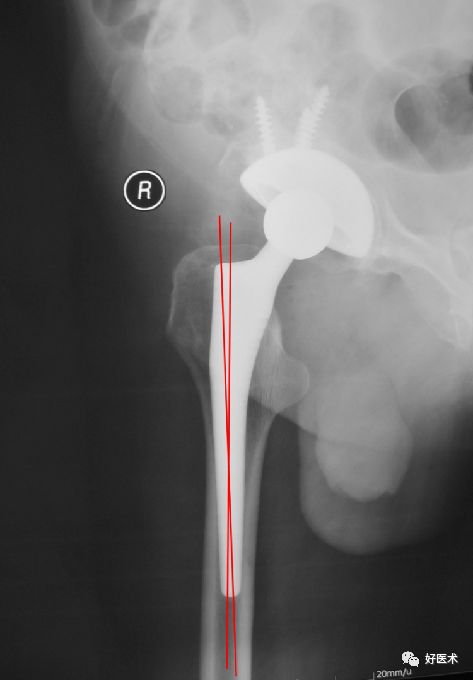

柄-髓腔轴线夹角

通过正位X 线片上测量假体柄长轴与股骨长轴间夹角来确定, 夹角≤3°为中心固定。

超出3°为内翻或外翻固定:

-

远端尖端在外侧-内翻;

远端尖端在内侧-外翻

柄-髓腔比

分别在正位和侧位X 线片上, 在三个水平( 小转子上缘、柄的中部、柄尖端近侧1 cm) 检测假体宽度与髓腔宽度之比(B/A×100%) 来确定。

正位片上>80%, 侧位片>70%为匹配满意。